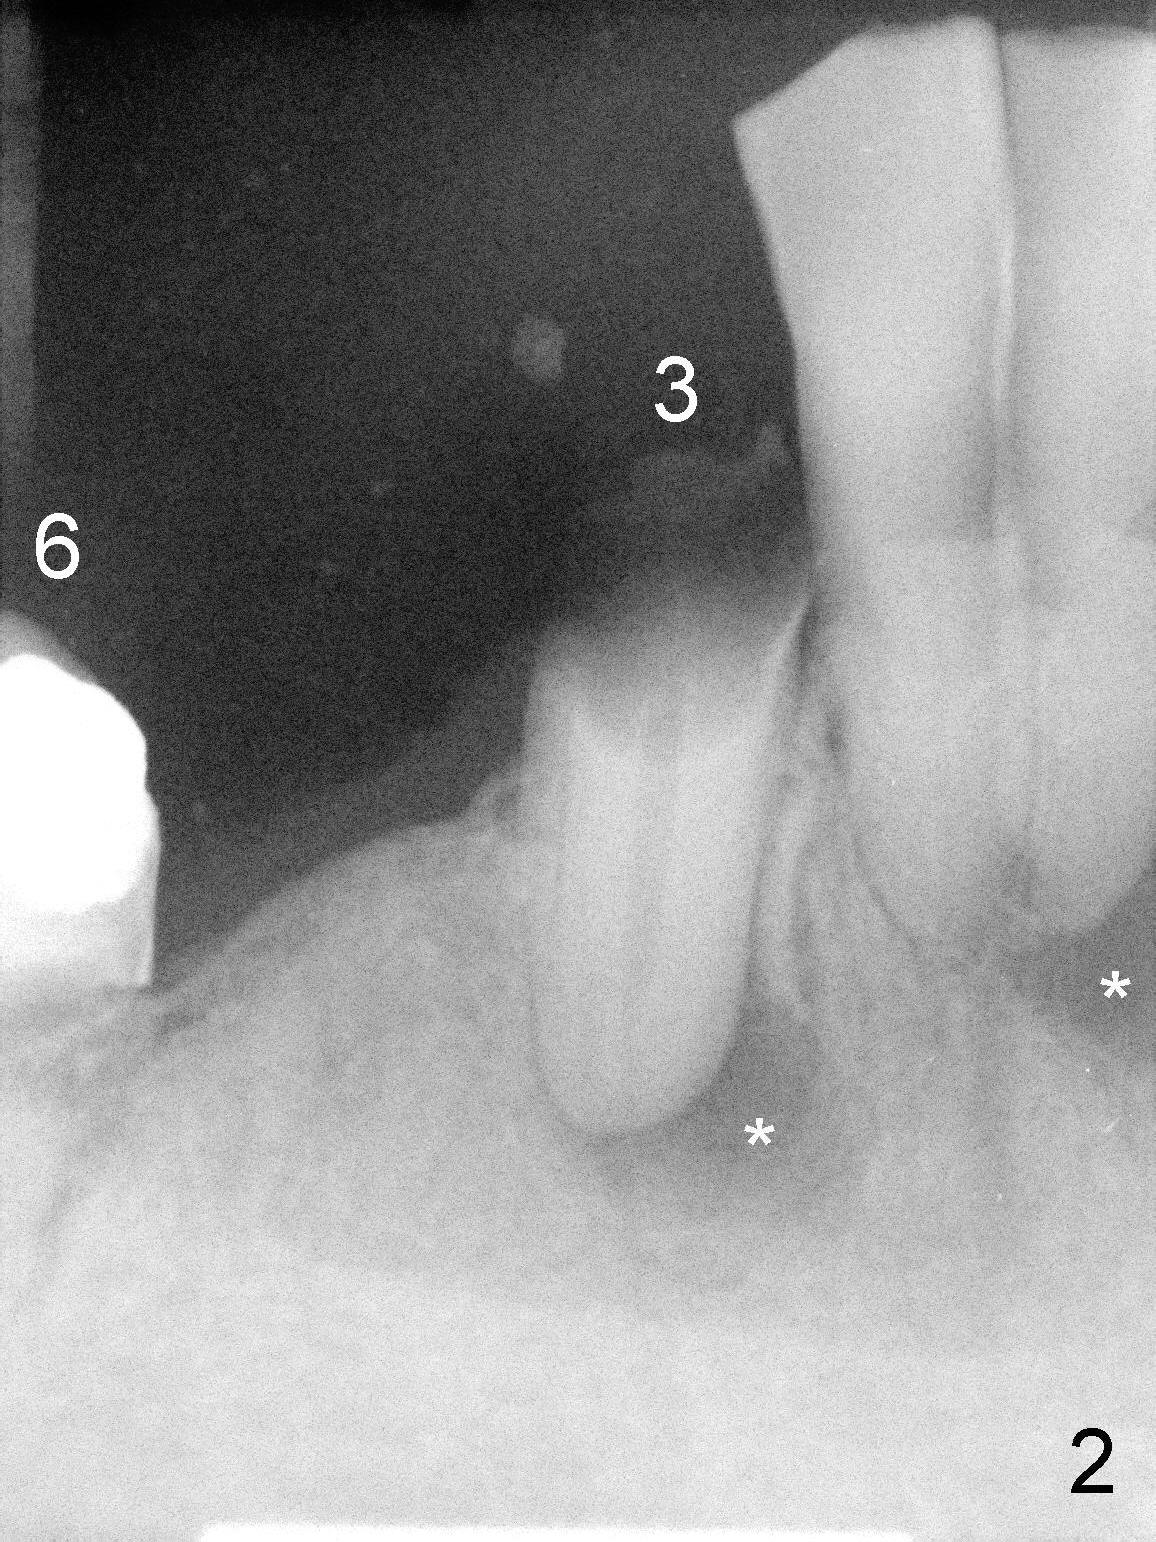

The lower right bridge (from canine (Fig.2: 3) to 1st molar (Fig.1: 6)) fails while a 77-year-old man is undergoing chemotherapy for urinary bladder cancer.  The abutments of the bridge are extracted without plan for implants (Fig.4).   Four months later, the patient returns for implants (Fig.3), but the ridge is narrow (Fig.5).  While 2 of 3x14 mm 1-piece implant are placed at the canine and 1st bicuspid sites, 2 piece ones at the 2nd bicuspid and 1st molar sites (Fig.6: 3.5x11 mm, 5x14 mm).  Soft (Fig.7-10) and hard (Fig.11) tissues heal 1 week (Fig.7) and 4 months (Fig.8-11).  There is minimal bone resorption 1 year 7 months post cementation (Fig.12,13, non-splinting).  It appears that narrow diameter implants are a valid solution to narrow ridge at the sites of the lower canine and premolar.  As long as there are enough implants for function, the crowns are not necessary to be splinted.  Surprisingly, the patient starts flossing after implant restoration.  Retrospectively an immediate provisional bridge should have been fabricated.

There appears to be no bone loss 2 years 5 months post cementation (Fig.14).  Gingival bands form around the implants at #27-29 three years 1 month post cementation (Fig.15 *).